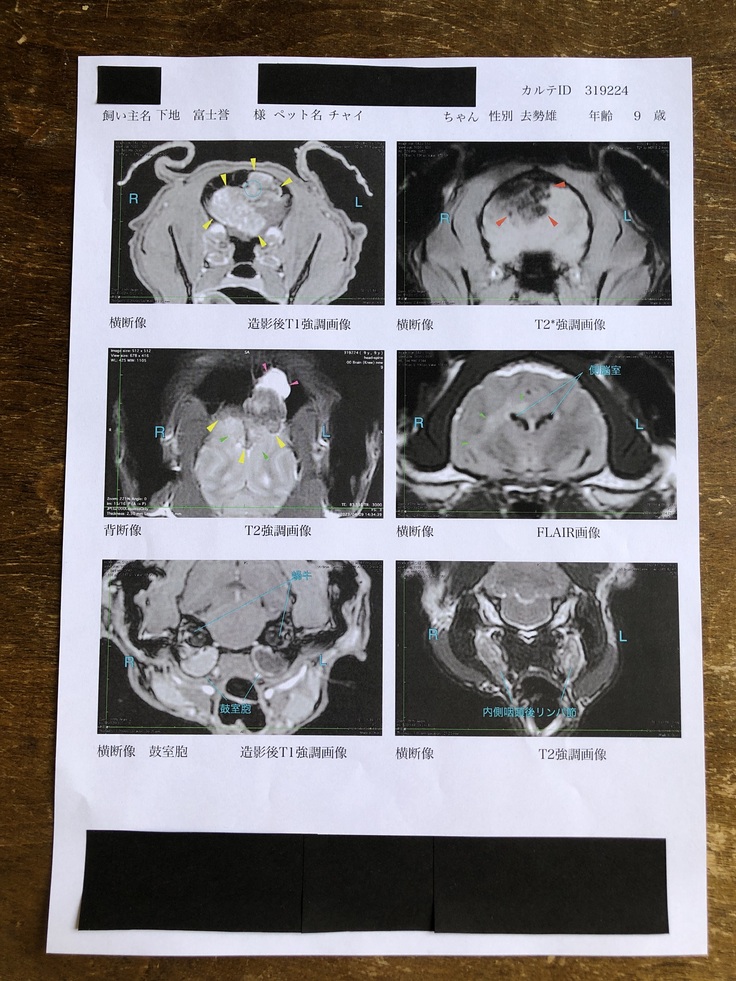

チャイの脳腫瘍は脳原発(脳から発症する)の骨軟骨種でした。

手術前のMRI画像で見た限りでは髄膜腫だと思われ、体に転移があるかどうかは現在分かっては居ません。

腫瘍摘出の際、脳内で大量の出血があり、血栓が出来たため術後3ヶ月頃を目安に経過を見るためMRIで検査をします。

その際、術後の経過と共に体も画像診断して転移の有無を確認する予定です。

検査の結果は脳腫瘍でした。

しかも「猫の脳腫瘍でここまで大きい腫瘍は見たことがない。ここまで大きいと手術は難しい」

仮に手術出来ても「かなり難易度が高い」と言われるほど大きい腫瘍で

・脳の大きさに対して1/3が腫瘍であること

・腫瘍の形がいびつ(ボコボコしてる)こと(石灰化しているかも)

・腫瘍が頭蓋骨まで浸潤していること

・術後の合併症のリスクも高いこと

・術中に急変するリスクがあること

術前の麻酔後にMRI検査をしたところ、脳腫瘍が更に大きくなっていて(腫瘍が脳の半分まで大きくなっていたそうです)術中のリスクは以前にも増して高くなると言われました。